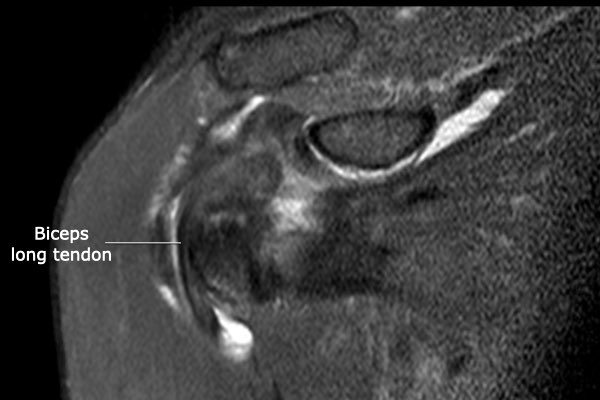

Hình ảnh

Chụp MRI khớp với chuỗi xung T1W xóa mỡ mặt phẳng axial và chuỗi xung PD mặt phẳng coronal.

Ghi nhận hình ảnh trật gân cơ nhị đầu về phía trong, nằm trong gân cơ dưới vai (mũi tên).

Có hình ảnh rách bán phần gân cơ dưới vai.

Trên ảnh PDW, ghi nhận khoảng trống chứa dịch tại vị trí bám tận xa của gân cơ trên gai và thuốc tương phản từ lan vào khoang dưới mỏm cùng vai – dưới cơ delta, phù hợp với hình ảnh rách toàn phần gân cơ trên gai.